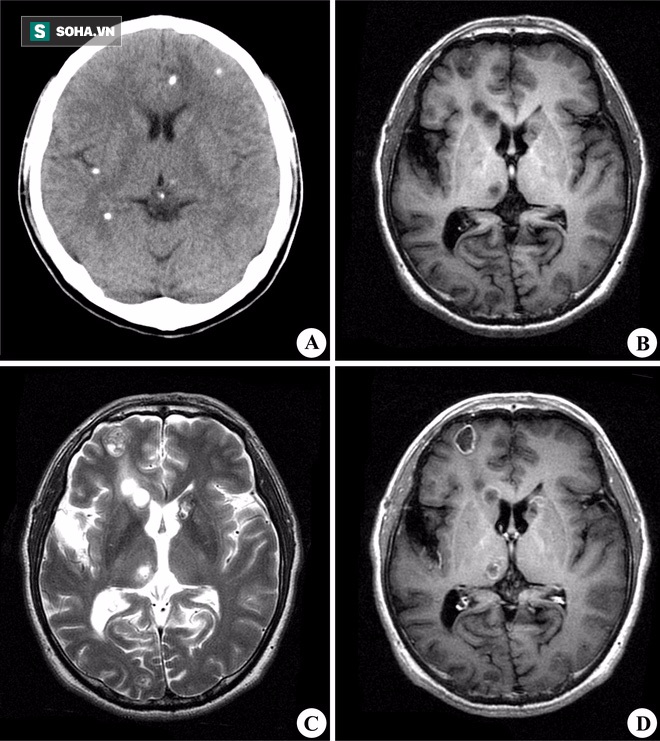

Ảnh chụp não có ký sinh trùng.

Người nhà chị đã nhanh chóng đưa đến Bệnh viện Vũ Hán, Hán Khẩu (TQ) để kiểm tra sức khỏe. Khi bác sĩ tiến hành kiểm tra sức khỏe, siêu âm và chụp ảnh não, đã bất ngờ phát hiện dị vật lạ trong não của chị.

Điều khiến mọi người bàng hoàng sợ hãi, dị vật đó chính là 3 con ký sinh trùng (thuộc loại giun sán) dài loằng ngoằng trong não của chị Hoàng, nhìn qua ảnh MRI có thể thấy rõ. Theo ý kiến của các bác sĩ BV Vũ Hán, chị Hoàng đã mắc bệnh nhiễm sán não (chủ yếu là sán dây lợn) do nhiễm ký sinh trùng thông qua ăn uống. Đây là loại bệnh ký sinh trùng não mãn tính, không loại trừ khả năng do sở thích ăn thịt nướng.